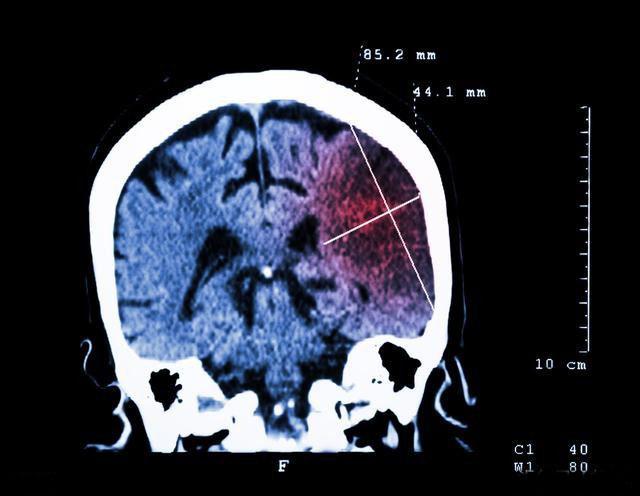

脑梗是大脑血管粥样硬化堵塞血管导致脑组织供血不足而引起的脑组织软化坏死所致的疾病,我们知道身体的一切机能都和大脑息息相关,无论是肌肉的运动还是对外界各种刺激的感觉都需要大脑的统一分析和指挥才能完成,因此,脑梗在发生前后都会有一定的特异性表现,做一些小的测验就能发现脑梗的早期症状,必要时到医院检查一下,在脑坏死还不太严重的时候就积极治疗,可以尽可能的保留大脑功能。具体的小测验如下。